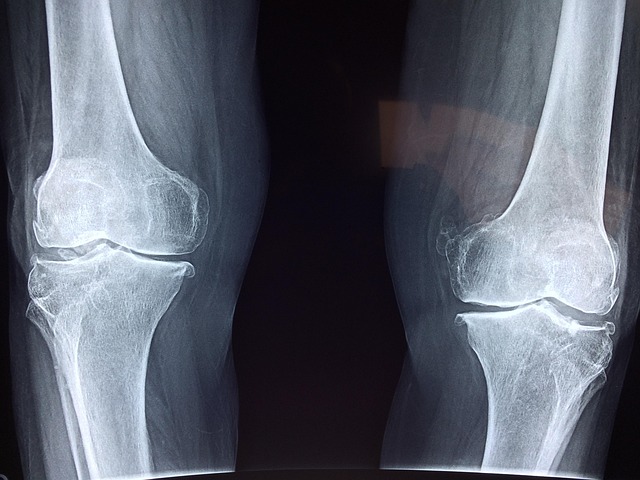

✅ 3) 연골 손상 및 관절염 진행

- MRI 또는 X-ray 검사에서 연골이 거의 닳아 없어진 경우

- 의사가 퇴행성 관절염 말기라고 진단한 경우